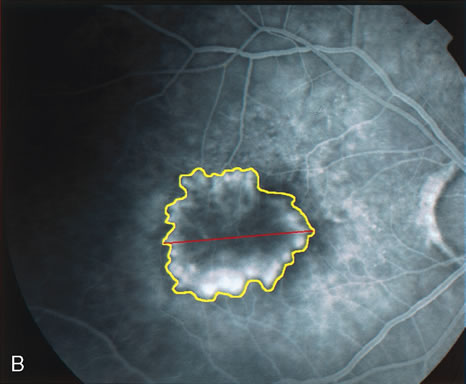

Fig. 19. A. Red-free photograph of the right eye of a patient with exudative angiomatous macular degeneration. B. Fluorescein angiography reveals the presence of subfoveal, classic choroidal neovascularization (CNV). The boundaries of the CNV are digitally traced (yellow), and the greater linear dimension of the lesion is measured (red) to guide the PDT.